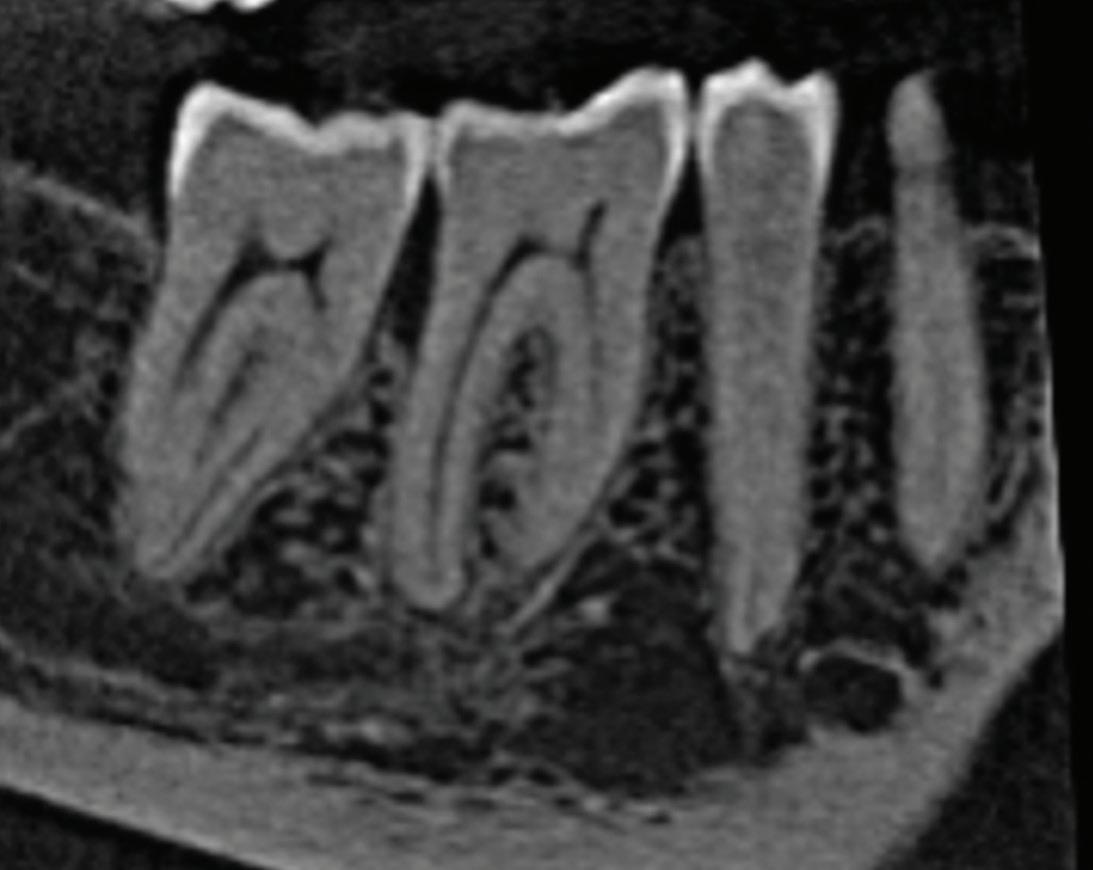

Fig 1. Proximity of root apices to vital structures. A. The periapical radiograph indicates that the apices of the mandibular right second molar and second premolar are in proximity to the inferior alveolar and mental nerves. B. A coronal CBCT image more clearly demonstrates the proximity of the molar apex to the inferior alveolar nerve. C. A coronal CBCT image more clearly demonstrates the proximity of the premolar apex to the mental nerve.

The inferior alveolar canal courses closely beneath the apices of mandibular molars, particularly second molars. Studies have shown that in more than 25% to 30% of patients, the inferior alveolar canal lies within 1 mm of the root apices of second molars; the prevalence is even higher in female and older patients due to reduced bone volume (Fig 1).8